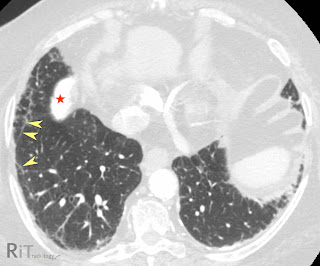

Axial CT image shows subpleural reticulation at the periphery of the lung bases bilaterally. Also note thin linear subpleural lines paralleling the pleural surface (arrowheads). There are several calcified pleural plaques in the diaphragmatic pleura (star).

- Curvilinear subpleural lines (as in our case) are lines running parallel to and a few millimeters beneath the pleural surfaces

- Thickening of interlobular septa and intralobular lines

- Dot-like opacities in subpleural lung may be an earliest CT finding of asbestosis